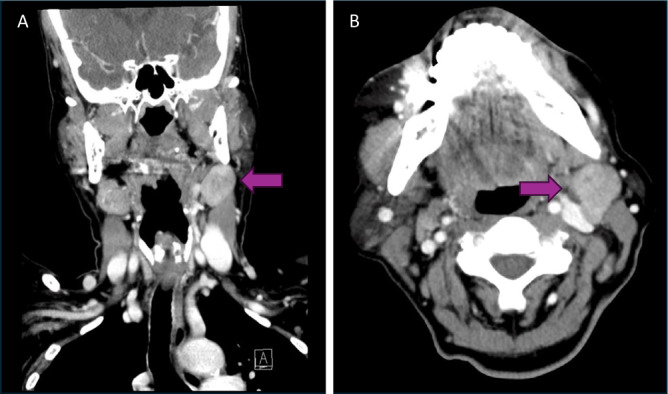

Objective: Mucoepidermoid carcinoma of unknown primary (MEC-UP) in the head and neck is a rare presentation of the most common salivary gland cancer. Cancers of unknown primary sites often have poorer prognoses than similar cancers with known primary. Few cases of MEC-UP have been reported; therefore, the objective of this report is an overview of the diagnosis and management of MEC-UP.

Methods: We present two patients with low-grade MEC-UP at a high-volume tertiary care institution in Ontario, and a database search returning 1560 citations of which five studies with seven MEC-UP cases were identified.

Results: Review of the limited cases suggest many clinicians use positron emission tomography-computed tomography (PET-CT) in addition to panendoscopy and targeted biopsies with consideration for diagnostic tonsillectomy in diagnostic work-up.

Conclusion: Like other salivary gland cancers, primary therapeutic surgical resection is recommended with low threshold for adjuvant radiotherapy to regions at high risk for harbouring the primary malignancy, especially in cases of high-grade histopathology.